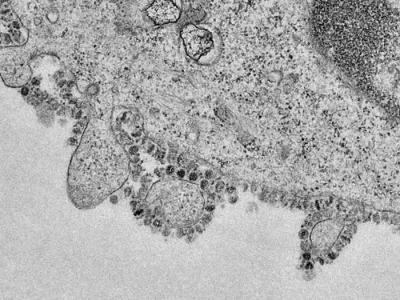

香港大学科学家发布首批新型冠状病毒繁殖

香港大学科学家发布首批新型冠状病毒繁殖的图像 显示感染2019-nCoV冠状病毒的细胞(...